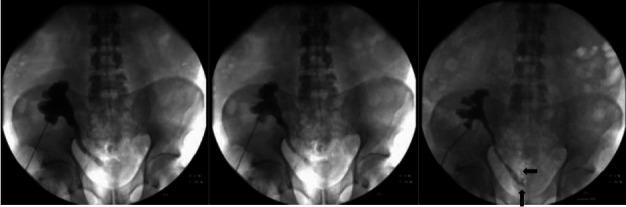

Urolithiasis is a rare urologic complication after kidney transplantation, and its diagnosis and treatment can be challenging for clinicians. In our 52-year-old male patient, graft hydronephrosis was found six months after transplantation. The patient had recurrent urinary tract infections followed by macrohematuria and an increase in creatinine levels. Computerized tomography revealed a 13-mm diameter stone in the ureter of the transplanted kidney as the cause of obstruction. Percutaneous nephrostomy was placed in the graft to solve the obstruction. Initial endoscopic treatment with a retrograde approach failed. An antegrade approach through a previously placed nephrostomy was not successful either. By a repeated retrograde approach, laser lithotripsy was performed successfully. The patient has been monitored for six months and has stable graft function without hydronephrosis or stones. As in our patient's case, the diagnosis and treatment of urolithiasis in kidney transplant patients is challenging, and minimally invasive procedures are the treatment of choice.

尿路结石是肾移植后一种罕见的泌尿科并发症,其诊断和治疗对临床医生来说具有挑战性。在我们这位 52 岁的男性患者中,移植后 6 个月发现移植肾积水。患者反复发生尿路感染,随后出现肉眼血尿和肌酐水平升高。计算机断层扫描显示移植肾输尿管内有一个 13 毫米直径的结石导致梗阻。在移植肾中放置经皮肾造口术以解决梗阻。最初采用逆行方法的内镜治疗失败。通过之前放置的肾造口术的顺行方法也没有成功。通过反复逆行方法,成功进行了激光碎石术。患者已接受了 6 个月的监测,移植肾功能稳定,无肾积水或结石。与我们患者的情况一样,肾移植患者尿路结石的诊断和治疗具有挑战性,微创程序是首选的治疗方法。